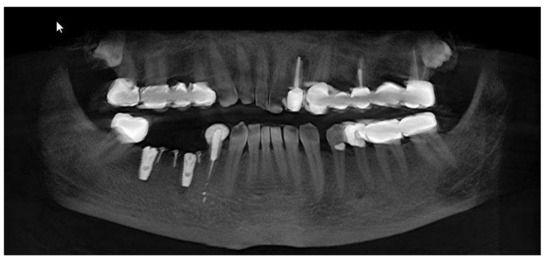

Clinical and CBCT aspects of patient from the test group, describing the stages of S-GBR technique and implant-prosthetic stage, are presented in Figure 1, Figure 2, Figure 3, Figure 4, Figure 5, Figure 6, Figure 7, Figure 8, Figure 9, Figure 10 and Figure 11. CBCT exam allows the evaluation of the horizontal alveolar bone defect and the position of the mandibular alveolar nerf (Figure 1A,B). Figure 1C,D show cross-sectional CBCT aspects of the implant sites. Figure 2 shows the narrowed mandibular alveolar bone with horizontal resorption. Figure 3 shows the exposed buccal surface of the alveolar ridge with severe horizontal resorption, after flap opening. The inserted implants (4.5 mm diameter, 11.5 mm length) and osteosynthesis screws (45° from the occlusal plan) are shown in Figure 4A. The placement of graft (autologous bone and xenograft) and collagen membrane is shown in Figure 4B. Figure 5A shows tension-free sutures, due to periosteal incisions alveolar ridge. Figure 5B shows clinical aspect at 7 months after surgery, with gingival tissue adherent on the reconstructed alveolar ridge. Figure 6 shows OPG aspect at follow-up of 7 months, with osseointegration of the dental implants. Figure 7A shows clinical aspect before osteosynthesis screws removal. Figure 7B shows clinical aspect after osteosynthesis screws removal. Figure 8A shows healthy peri-implant soft tissues. Figure 8B shows repositioning key for perfect position of abutments. Figure 10A,B show clinical aspects of implant-supported prosthetic restoration. Figure 11A,B show CBCT aspects of Osseo integrated dental implants at 24 months follow-up.

Figure 1.

(A,B) Pre-operative CBCT aspects. (A) Narrow residual alveolar ridge. (B) Analysis of the mandibular nerve position. (C,D) Pre-operative CBCT aspects (cross-sectional).